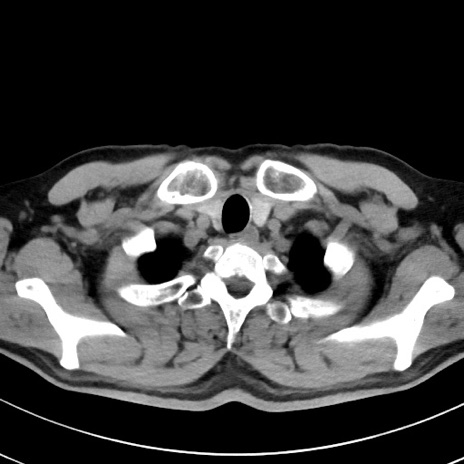

【腹部TIPS】症例29 参考症例 CT(横断像)

症例

70歳代男性